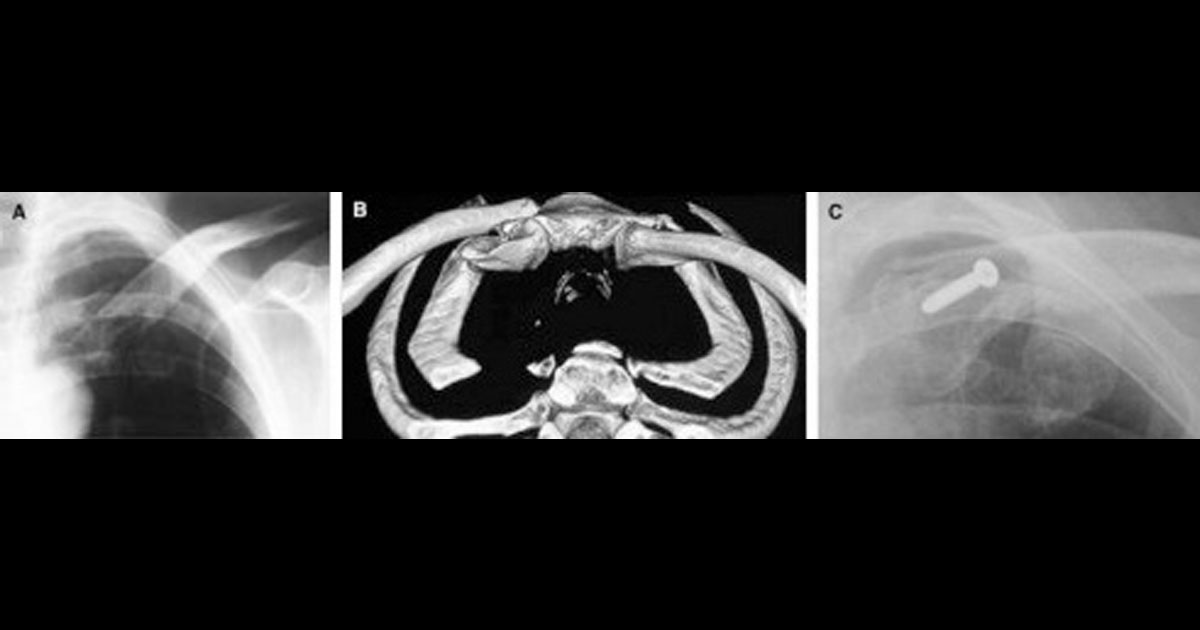

Five adult patients were identified who had operative treatment for a displaced medial end clavicle fracture. All were male with a mean age of 43 (25–52) years. Three were right-hand dominant, and in 4, the injury affected their dominant side. The cause was typically the result of a high energy injury (motorcycle 3, motor vehicle accident 1, rugby 1), and all were isolated injuries. Preoperative computed tomography (CT) scans were obtained in 2 patients to assess the amount of anterior displacement. The 3D reconstructions were able to define the deformity accurately in these patients.

Recently, Throckmorton et al reviewed 57 medial end clavicle fractures retrospectively in 55 patients that presented to a level 1 trauma center. Treatment was nonoperative, except in 4 where an open fracture was present. The majority was the result of high energy trauma, such as motor vehicle accidents, and this finding was supported by our study and others. Ninety percent of their patients sustained multisystem injuries with an associated 20% mortality rate. Medial end fractures comprised 9.3% of all their clavicle fractures, a higher incidence than that reported previously. This was accounted for by the higher use of CT scans in the trauma setting, where 22% of fractures were seen only on CT scans, but not on radiographs. CT scans can also be useful for determining the amount of displacement, especially in the coronal plane, which may not be readily seen on chest x-rays alone (Figures 1 and 2). In their study, 44% of medial end fractures were minimally displaced (<2mm), 23% had 2-10 mm, and 33% had >10 mm of displacement. Disappointingly, after a mean of 15.5 months, the majority of patients still reported mild (25%), moderate (22%), or severe (6%) pain.